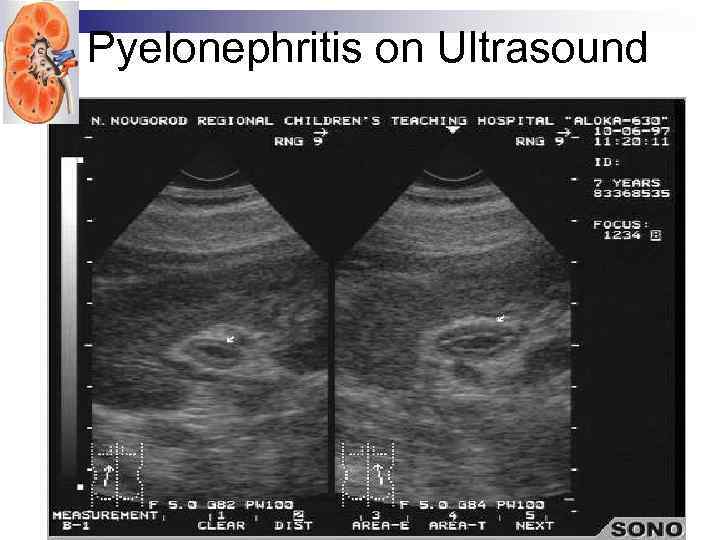

UTI. Ultrasound Advantages • Measures renal size and shape Identifies hydronephrosis, structural or anatomic abnormalities and renal calculi • No radiation • Disadvantages • Not reliable to detect vesicoureteral reflux, renal scarring or inflammatory changes

UTI. Ultrasound Advantages • Measures renal size and shape Identifies hydronephrosis, structural or anatomic abnormalities and renal calculi • No radiation • Disadvantages • Not reliable to detect vesicoureteral reflux, renal scarring or inflammatory changes

Pyelonephritis on Ultrasound

Pyelonephritis on Ultrasound